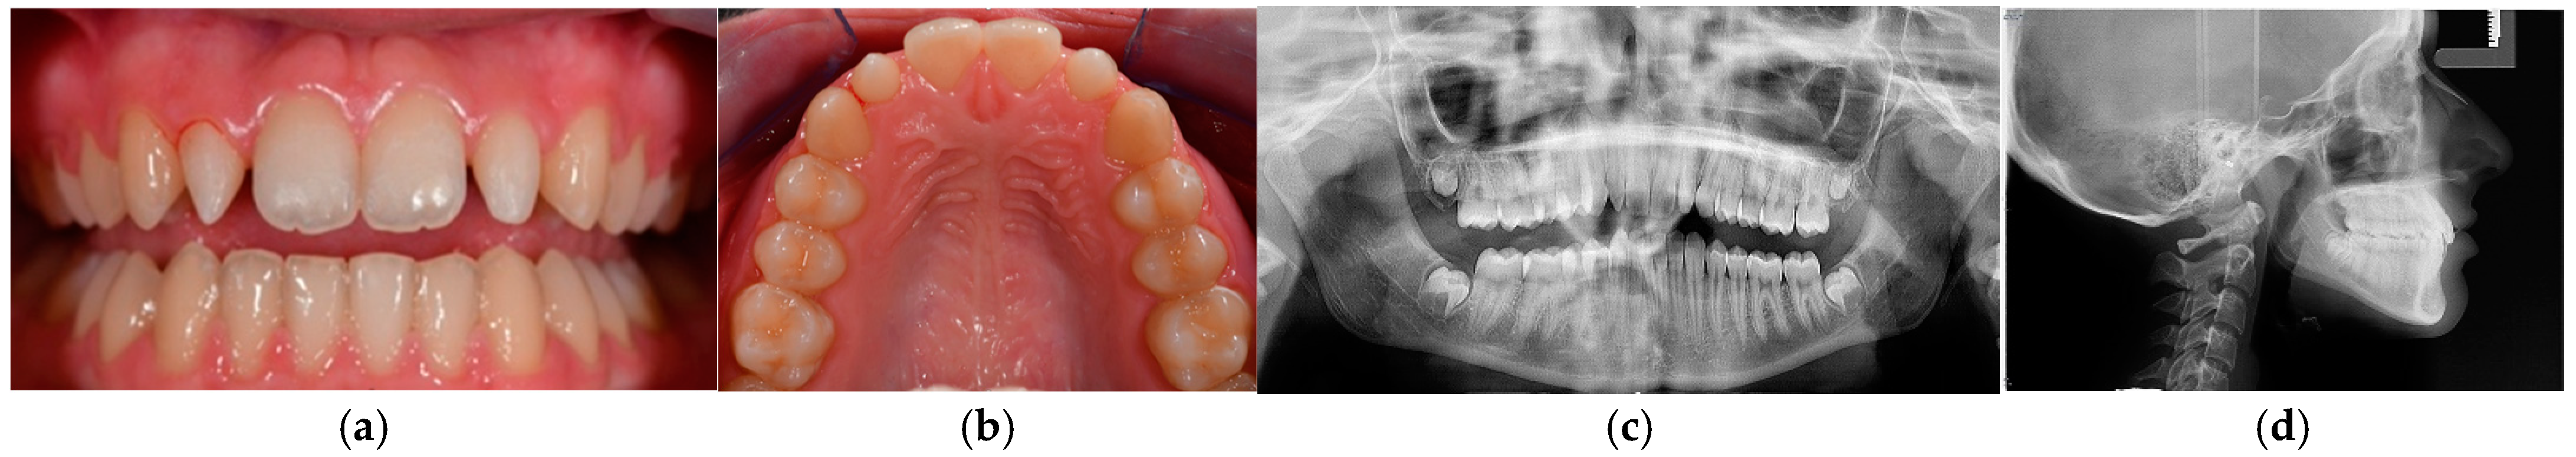

Figure 1.

(a) Frontal view of teeth with a slightly open mouth to elucidate the conoidal teeth (12 and 22). (b) Occlusal perspective of the patient’s maxillary arch. (c,d) Radiographic evaluations.